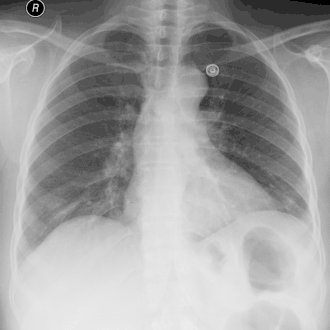

CT-thorax laat een grote rechtszijdige hydro-pneumothorax zien, ontstaan door empyeem.

Pijl A: lucht, B: vocht | ||||